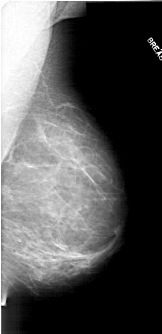

A_1711_1.LEFT_CC

RIGHT_CC LINES 6166 PIXELS_PER_LINE 3091 BITS_PER_PIXEL 12 RESOLUTION 43.5 NON_OVERLAY